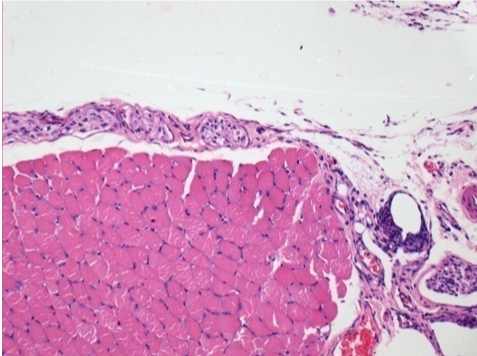

10 days after Endopeel Injection

10 days after Endopeel Injection 0.1ml in the right pretibial muscle.

Here you may see the formation of the vacuoles which are surrounded by lymphocytes. Vacuoles are different from tissue necrosis . The presence of lymphocytes is related to the permeability of the cell membranes.

L : Control-100xD10

R:100xD10

R :200xD10

R :400xD10